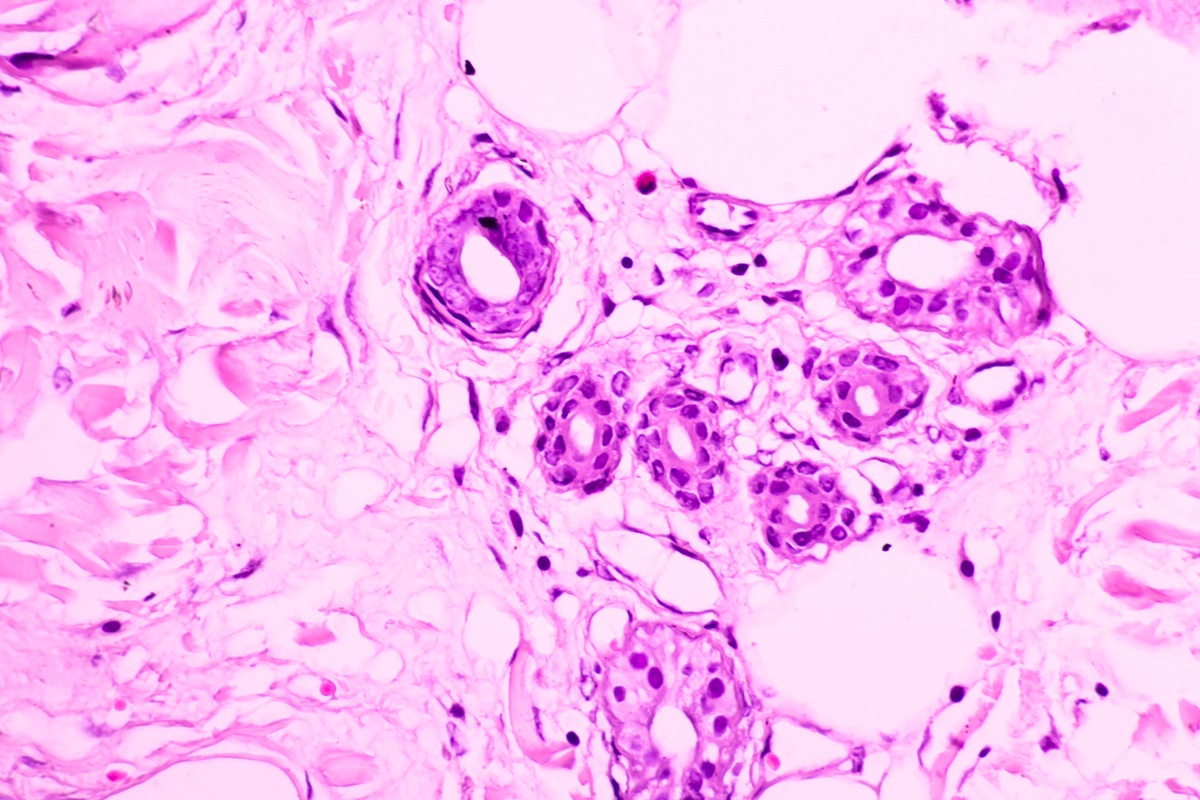

ガン細胞は活性酸素や放射線、化学物質などといったさまざまなストレスによって正常細胞(遺伝子)が傷つけられてできた異常細胞のひとつです。

これらの異常細胞は、基本的に免疫細胞で除去されたり、「アポトーシス」(細胞の自死)や「オ—トファジー」(不要細胞の自己消化) などによってリサイクルされたりして、ガン化は防がれているのです。

まだ解明されていないことは多くありますが「ガン化」についてTMCA理論では、「ミトコンドリア」「自己免疫」「アポトーシス/オートファジー」に注目しています。

しかし、機能が低下したり老化したりしたミトコンドリアから過剩な活性酸素がつくられれば処理しきれなくなり、多くの細胞が傷付けられ異常細胞が増えてしまいます。

ミトコンドリアの機能異常によって生じた「過剰な活性酸素」は、ガン細胞を含め老化やさまざまな疾病の原因のひとつとなるのです。

つまり、正常細胞がガン細胞になるのは、ミトコンドリアの呼吸代謝異常によって「正常細胞の傷害が蓄積される」からです。

❸正常に機能しない異常細胞が、体内の至る所で発生する。

❺一部、残ってしまった異常細胞は、情報伝達物質の放出や細胞表面に異物を提示するなど、細胞が正常に機能しないまま増殖を始める。

❼再度、一部残ってしまった異常細胞は、さらに免疫回避などの工夫をしながら増殖して細胞塊を形成していく。

❾免疫細胞やアポト—シス、オ—卜ファジ—などによる除去を何度も免れた異常細胞は、大きな腫瘍へと成長し、転移したりする。